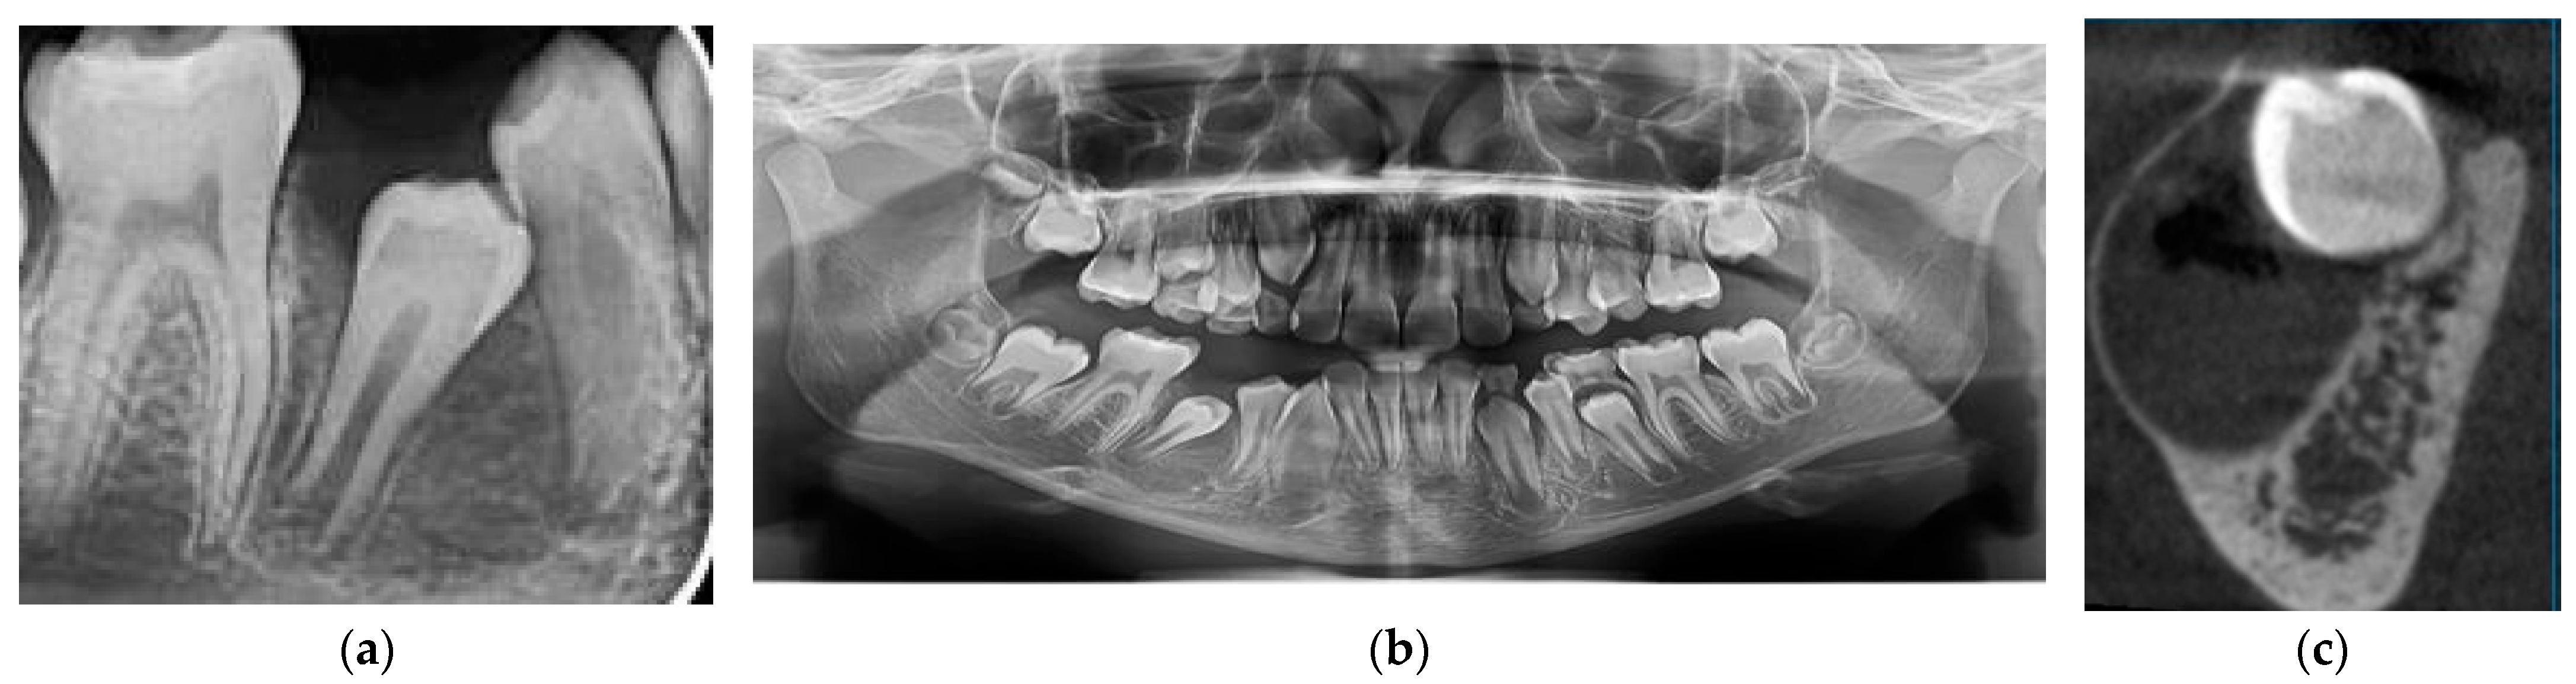

2.2.1. Case 1

2.2.2. Case 2

2.2.3. Case 3